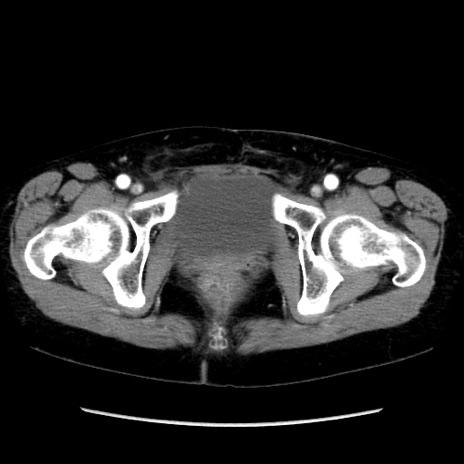

冠状断像

矢状断像